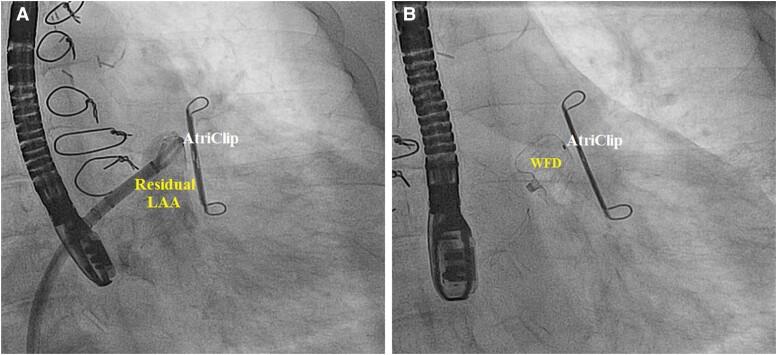

In patients with non-valvular atrial fibrillation, the vast majority of thrombi originate in the left atrial appendage (LAA). Thus, occluding the LAA significantly reduces one's risk for developing an ischaemic stroke. To date, many different surgical methodologies in LAA occlusion (LAAO)/exclusion have been studied and utilized. Unfortunately, patients are often left with incomplete closure of their LAA, leaving behind residual lobes that continue to allow thrombus formations. With the recent rise in percutaneous approaches and devices such as the WATCHMAN FLX, there have been proven success rates in achieving total closure of the LAA. Reports and investigations regarding the utilization of WATCHMAN FLX devices in patients with surgically incomplete LAAO remain limited.

We present three cases of patients who had previously undergone surgical exclusion of the LAA yet unfortunately were left with residual LAA that continued to place them at high risk for an ischaemic stroke. Percutaneous LAAO with the WATCHMAN FLX was utilized to successfully achieve complete sealing of the residual lobes in failed LAA surgical closures.

Our multicentre case series elucidates that an increased risk of stroke due to surgical LAAO failure is a real-world possibility that is likely to be encountered in clinical practice. We demonstrate in this series how the WATCHMAN FLX may provide a feasible and safe method to supplement a surgically incomplete LAAO to allow for improved ischaemic stroke and systemic embolization risk reduction.